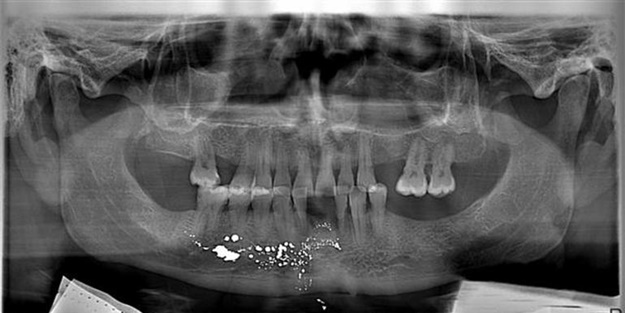

"Dişim ağrıyordu, ilçedeki polikliniğe gittim. İğne vurarak ön dişimi çektiler. Dişimdeki ağrı azalmadı. Ertesi gün aynı polikliniğe giderek ağrımın dinmediğini söyledim. Hap verdiler ve 4 gün boyunca kullanmamı istediler. 4 gün sonunda ağrım iyice arttı. Tekrar gittim, dişimin röntgenini çektiler ancak bana hâlâ ne olduğunu söylemediler. Bu arada çenemde şişlik oluşmaya başladı. Dudağım kabardı. Tat alamamaya başladım. Doktorla birlikte Nevşehir'de başka bir doktora gittik. Burada çenemdeki enfeksiyonu akıtacaklarını söyleyerek bir ameliyat yaptılar. 3 gün sonra tekrar gelmemi söylediler. Hâlâ bana ne olduğunu söylemiyorlar, 'Ufak bir operasyon, korkacak bir şey yok' diyorlar. İkinci ameliyat için gittiğimde benden 'ameliyat riskli, bütün riskleri göze alıyorum' diye muvafakat istediler. Ben de 'Bana bir şey olursa doktorum sorumludur' diye yazdım. Ameliyat etmekten vazgeçtiler. Bana, dişimi çekmek için anestezik madde enjekte edilirken yanlışlıkla cıva karıştığını söylediler. Korktum, hemen devlet hastanesine gittim. Oradan Kayseri'ye daha sonra da Ankara'ya sevk edildim."

Günay, Ankara'daki ilk tedavisinin 1 ay 3 gün sürdüğünü, hâlâ cıvadan kurtulamadığını, çenesinde şekil bozukluğu oluştuğunu ve konuşmakta zorluk çektiğini belirtti. Günay, "Zaman zaman Ankara’ya giderek kanımdaki cıva oranını ölçtürüyorum. Cıvanın vücudumdan tamamen atılması için uzun bir süre tedavi görmem gerekiyor. Savcılığa şikâyette bulundum. Doktorun cezalandırılmasını istiyorum" dedi.